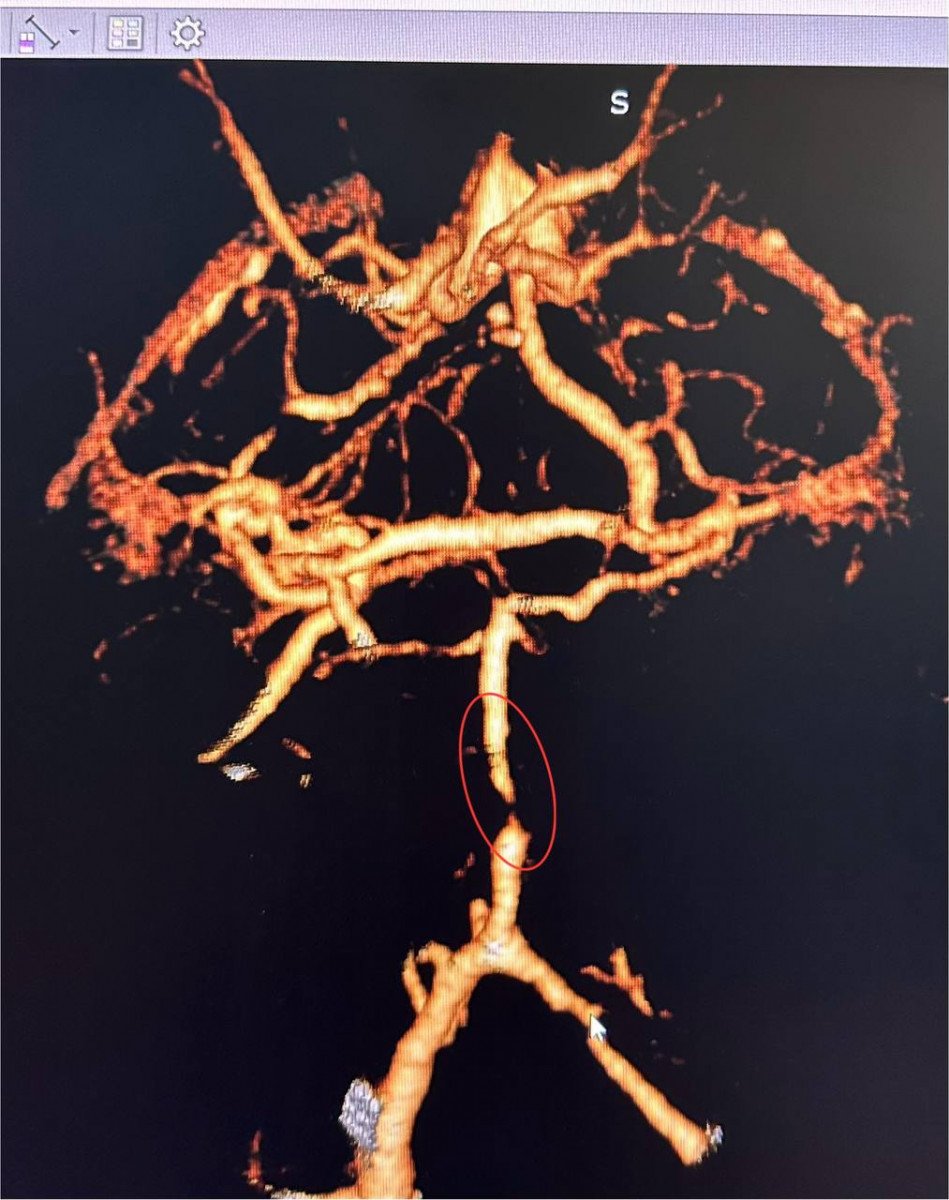

Як розповів завідувач рентгенендоваскулярного блока лікарні Олександр Скрипка, це був один з найскладніших випадків - ураження стовбурової частини мозку. Базилярна артерія була майже повністю закрита атеросклеротичною бляшкою. Такі інсульти належать до найбільш небезпечних, а за відсутності термінової допомоги навіть шанси на виживання мінімальні.

Фахівці прийняли рішення оперувати та провести ангіопластику артерії. Кластерна лікарня №10 має досвід такої методики лікування в кардіології при атеросклерозі коронарних судин, але застосування її для мозкових судин - це інноваційна технологія в масштабах України.

Операція тривала близько 60 хвилин. Звужену артерію розширили за допомогою спеціального балона, а потім застосували балон з лікарським покриттям.